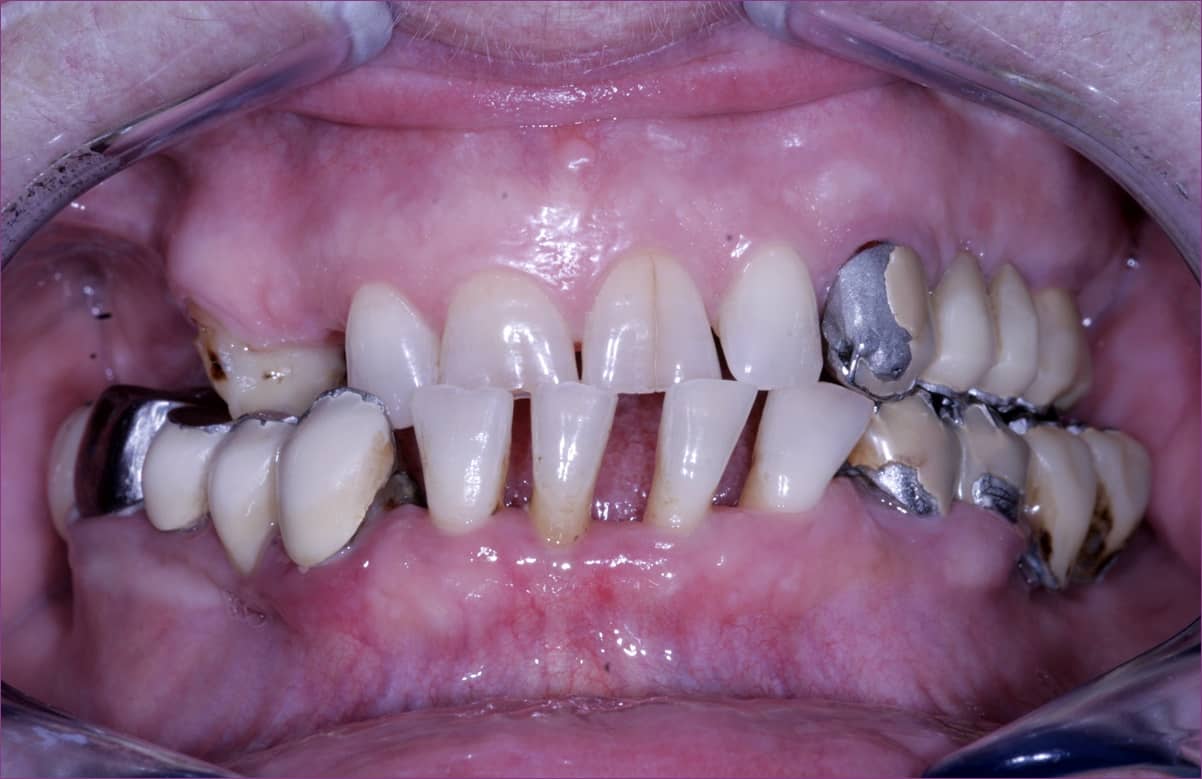

Dr. Sápi Béla fogorvost, a konzerváló fogászat és fogpótlástan szakorvosát azért kereste fel az idős hölgy, mert elégedetlen volt pár évtizede készült fogpótlásaival. (Mint később kiderült, páciensünk régóta szenvedett különböző krónikus fájdalmaktól, többek között fejfájástól is.)

Valóban, túlzás nélkül állíthatjuk, hogy a pótlások megértek a cserére, mi több, komoly rehabilitációra volt szükség.